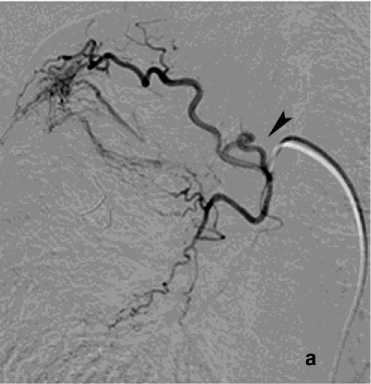

Первым этапом в процессе диагностики бронхоскопии через фибробронхоскоп выполняли промывание трахеи холодным физиологическим раствором, инъекции адреналина (рис. 5). При наличии и доступности определённого источника кровотечения использована электрокоагуляция с ис- сечением опухоли бронха 4 (2,7%), бужирование и стентирование бронха 11 (7,3%). При интенсивном кровотечении в 13 (8,7%) случаях выполняли брон-хоблокацию. Удаление блокатора осуществляли на 5–8 сутки. В одном случае бронхоблокация сочеталась со стентированием аорты. Проведённый анализ ангиограмм позволил выявить косвенные признаки ЛК. В большинстве случаев наблюдалось усиление кровоснабжения зоны поражения независимо от выявленной патологии (рис. 6, а). Локализация сосудистых изменений соответствовала данным, полученным при таких диагностических методах как ФБС и КТ. Эти ангиографические признаки не имеют прямого отношения к ЛК, но достаточно полно характеризуют его причину в силу специфичности семиотики различных лёгочных заболеваний. Прямые признаки экстравазации мы наблюдали в одном случае при наличии аортобронхиального свища (рис. 9, а).

Рисунок 5. Эндоскопическая картина лёгочного кровотечения. Источник кровотечения – бронх В3 справа и средне-долевой бронх правого лёгкого: а – кровь в просвете бронха В3 справа; б – кровь в просвете средне-долевого бронха справа

Figure 5. Endoscopic view of pulmonary hemorrhage. Bleeding source: B3 bronchus on the right and middle lobe bronchus of the right lung: a – blood in the lumen of the right B3 bronchus; б – blood in the lumen of the right middle lobe bronchus